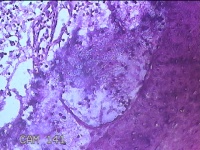

下唇肿物

性别

女

年龄

9岁

临床诊断

唇粘液囊肿

一般病史

下唇肿物1月

标本名称

大体所见

灰白暗红色肿物0.8x0.5x0.2cm一个,表面糜烂。